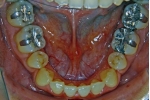

治療中